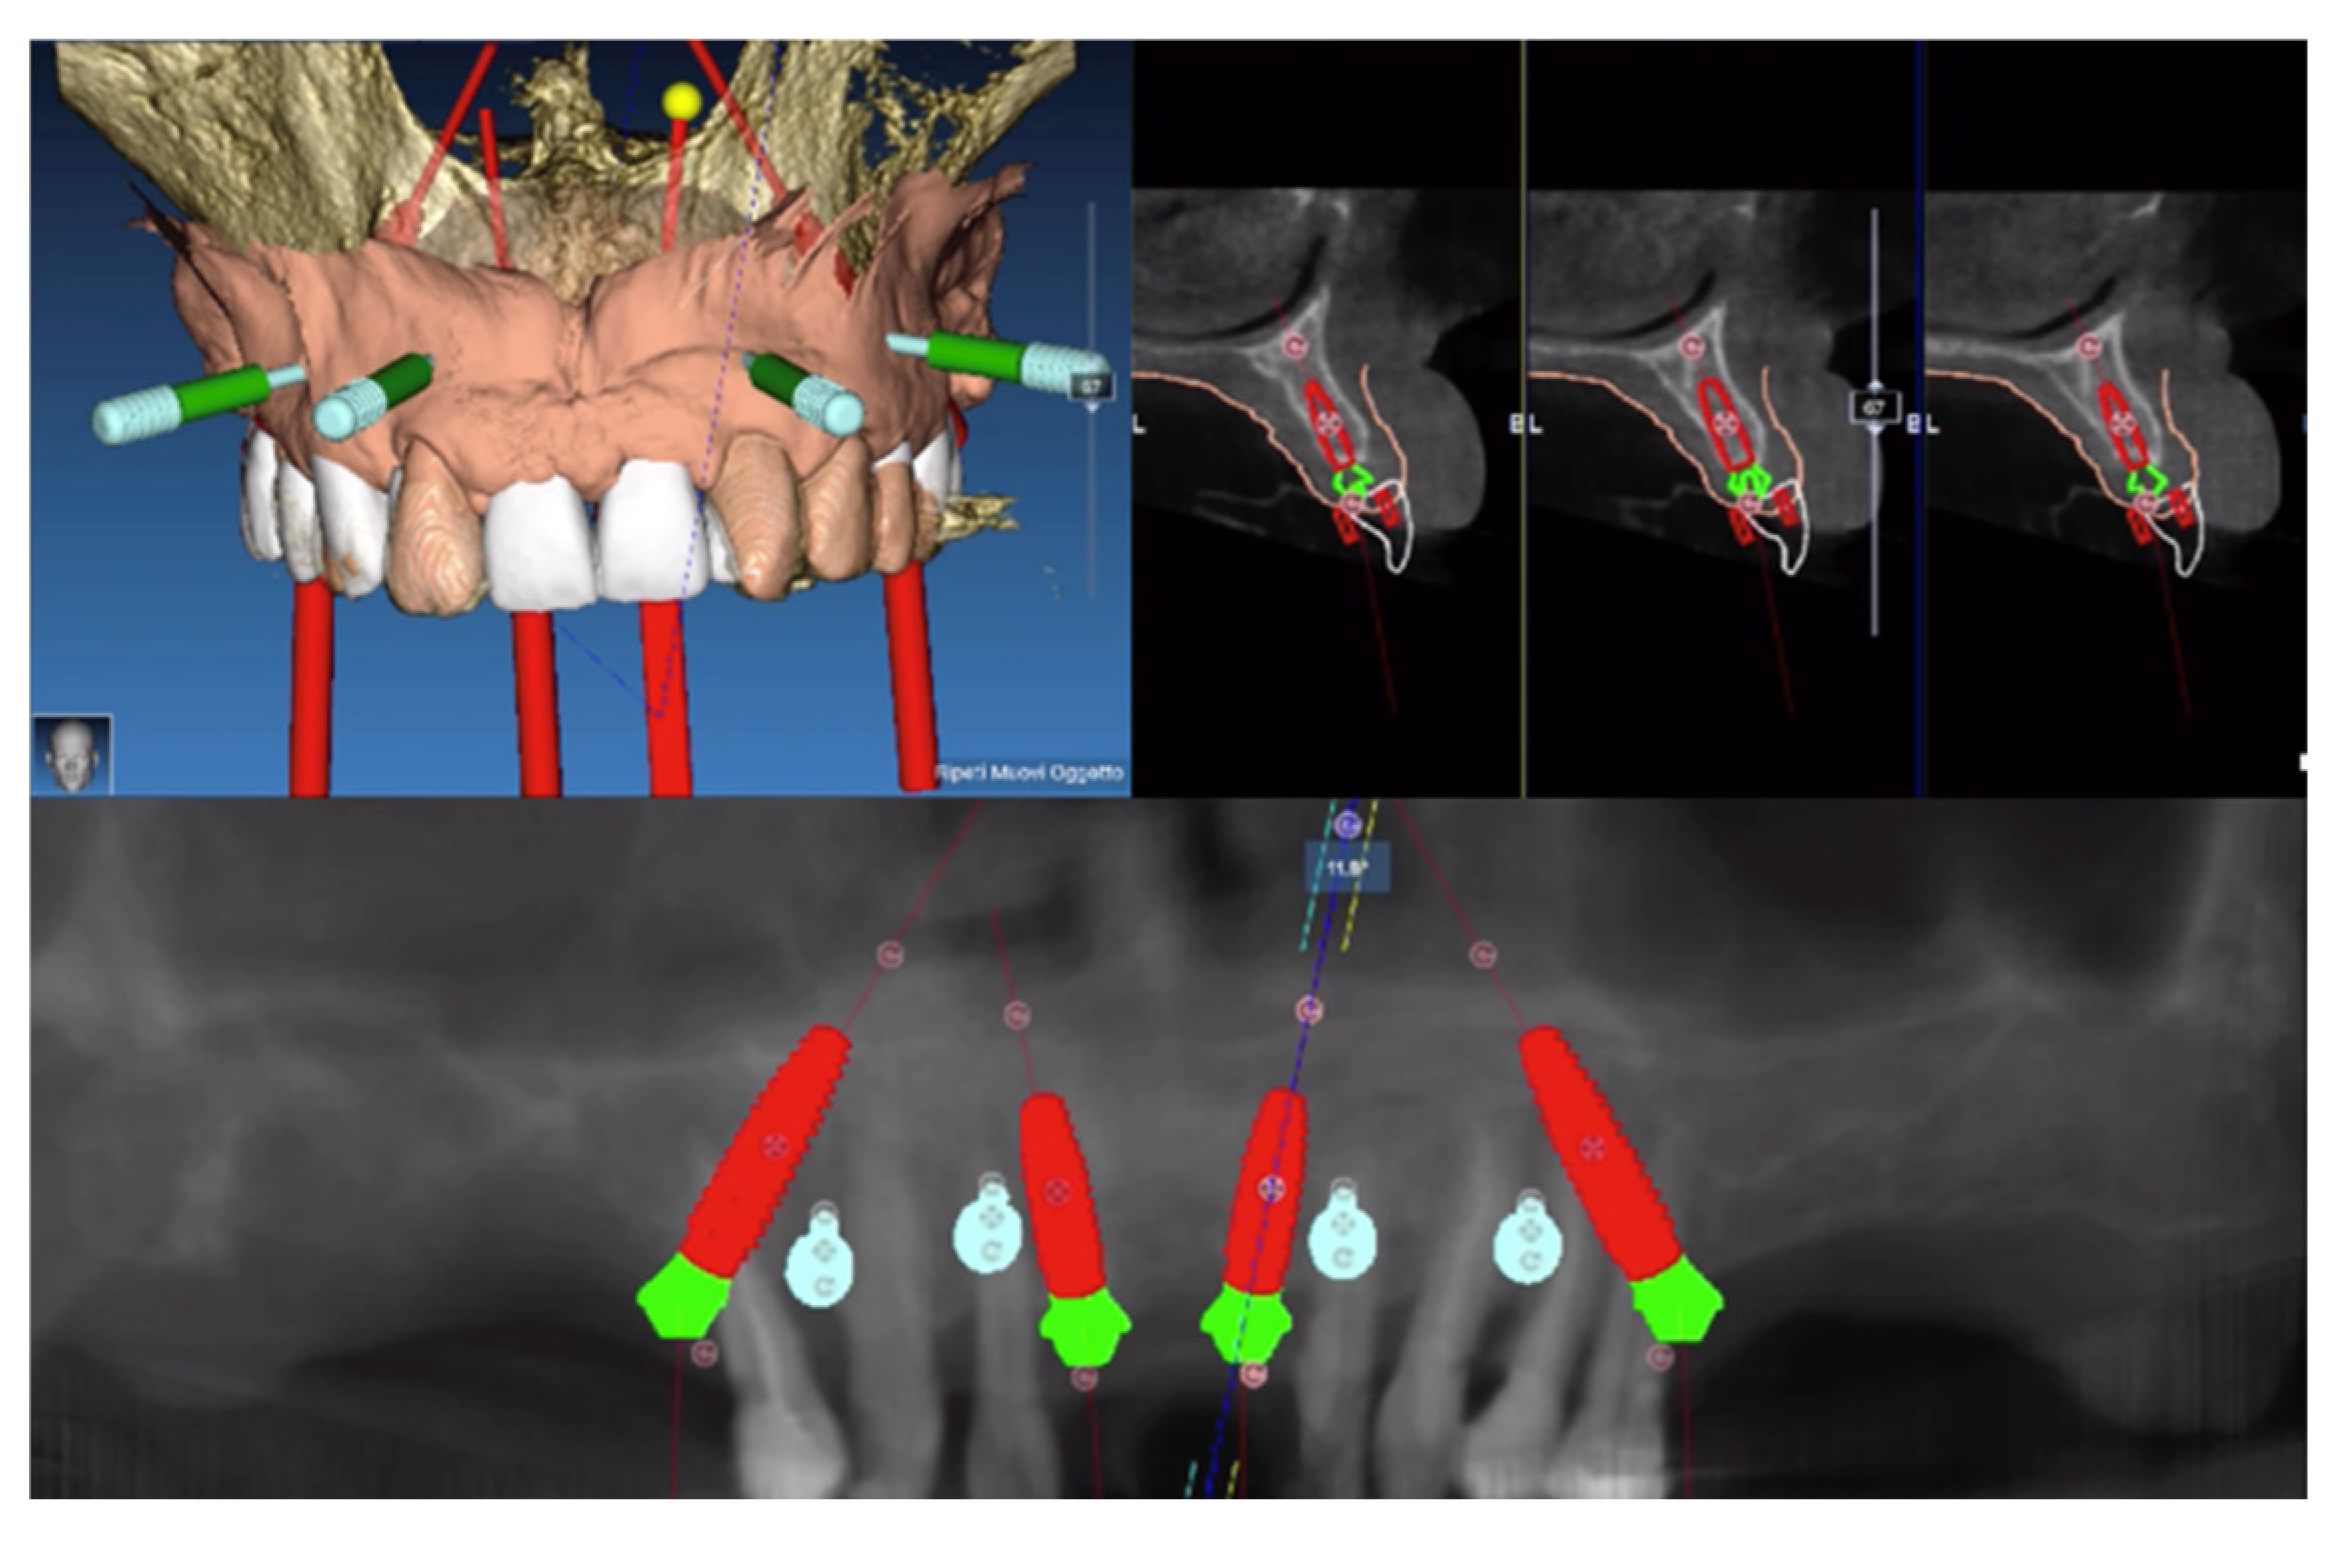

2. Materials and Methods

- 15: 4 × 15 mm 30°

- 11: 3.5 × 11.5 mm 17°

- 21: 3.5 × 11.5 mm 17°

- 25: 4 × 13 mm 30°